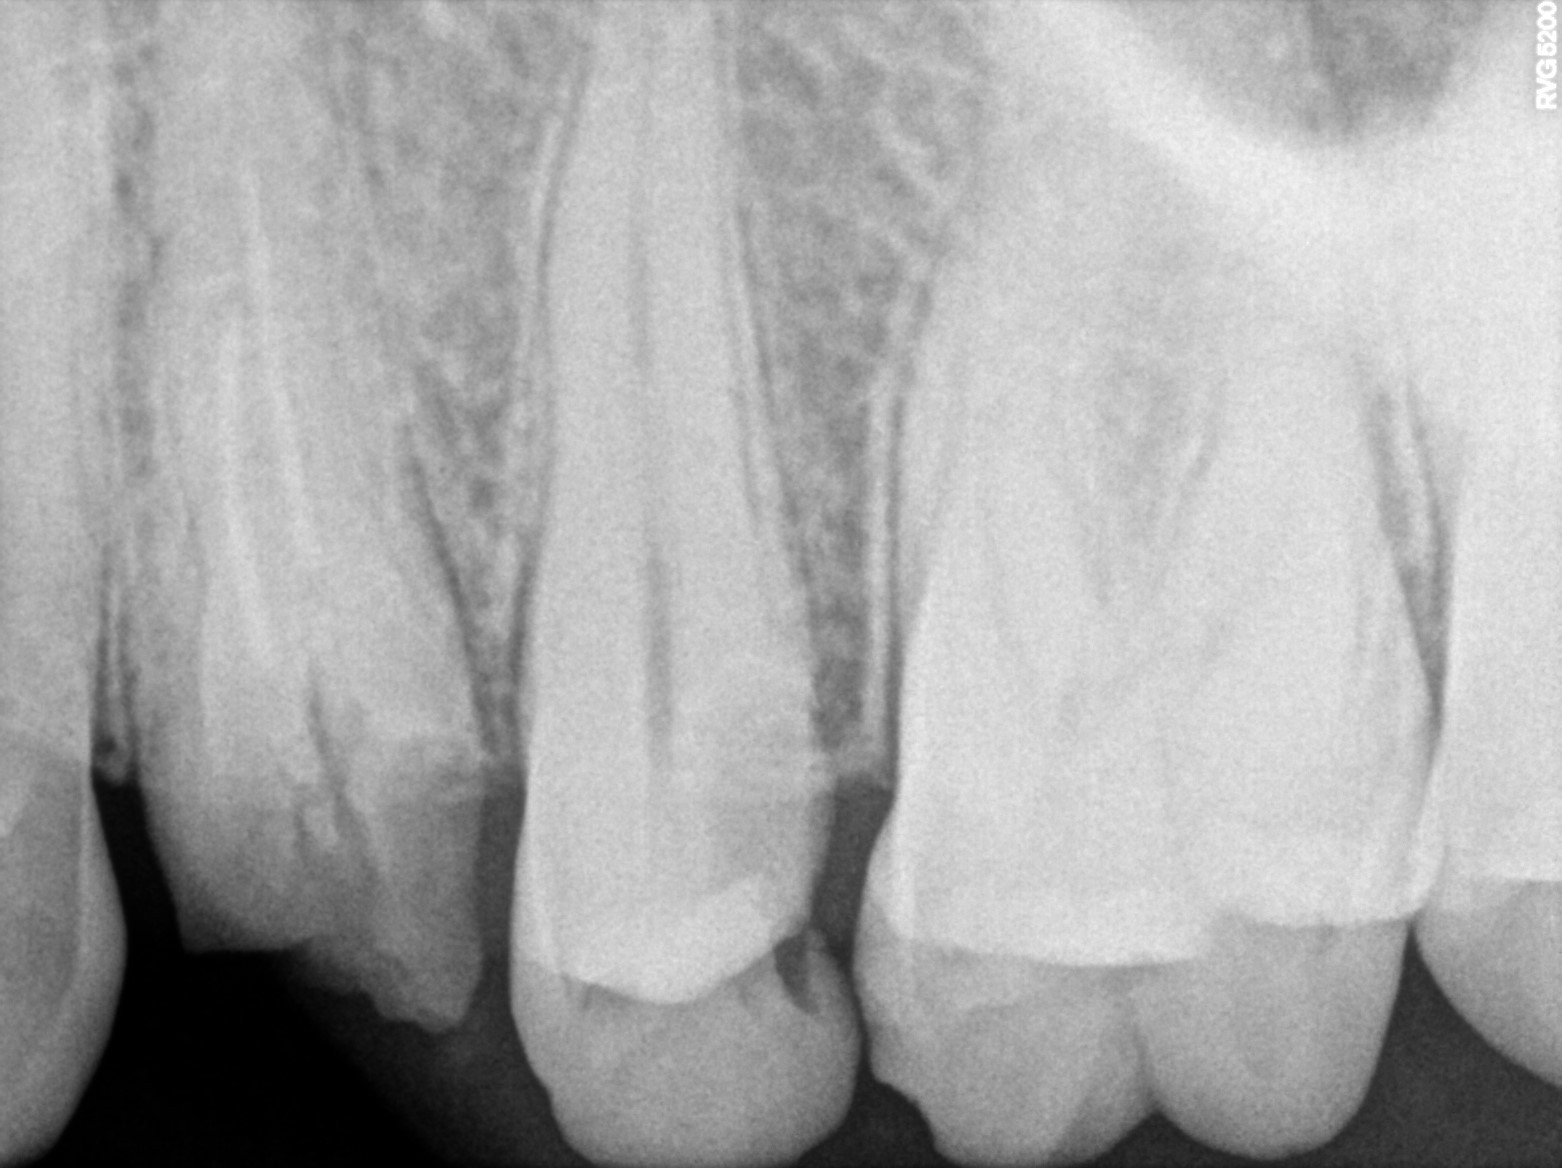

Dental Radiographs FHIR: DocumentReference · LOINC 24641-7

xray_1772549628_0.jpg

xray_1772549628_1.jpg

| Necrosis of dental pulp | K04.1 | 234946006 | resolved | 2026-03-04 | svrct done with 25 | |

| Necrosis of dental pulp | K04.1 | 234946006 | resolved | 2026-03-03 | adv rct with 25 |

| Root canal treatment | 234780006 | — | ##25 | 2026-03-04 | completed | svrct done with 25 | |

| Root canal treatment | 234780006 | D3320 Endodontic therapy, premolar tooth | ##25 | 2026-03-03 | completed | adv rct with 25 |